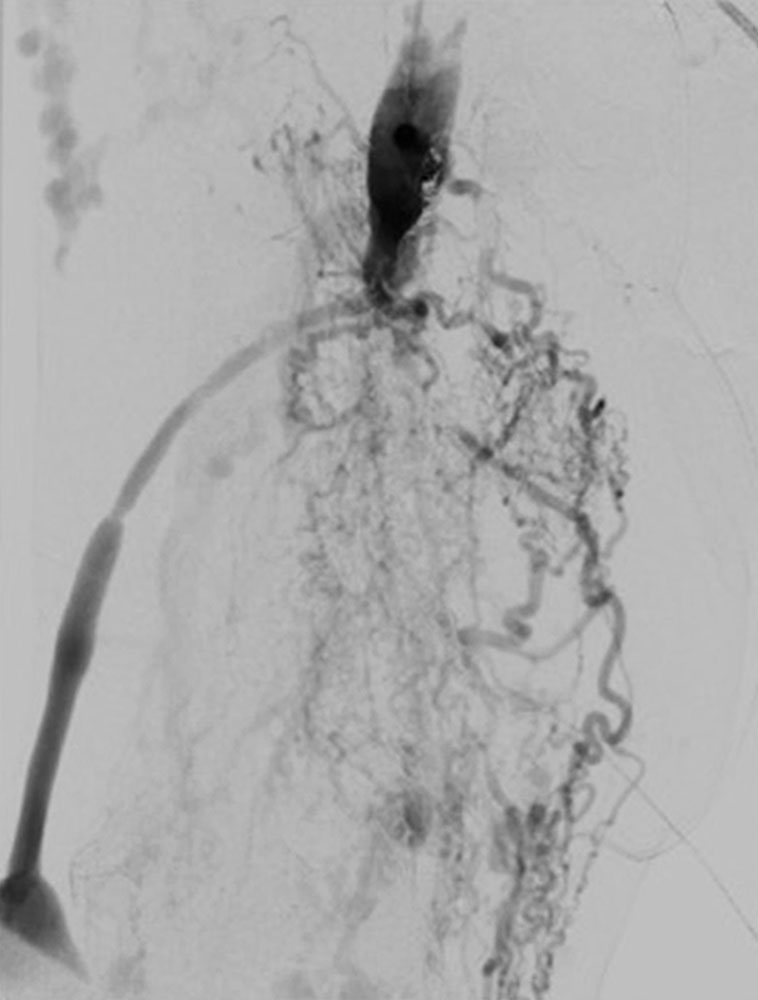

Bei arteriovenösen Malformationen hat sich die Technik der Skelettierung der Gefäße mit Unterbindung von zuführenden Fistelästen nicht bewährt, da sich häufig über Kollateralverbindungen eine identische Füllung und Hämodynamik ergeben kann.

Inzwischen werden resezierende Verfahren an den Gefäßen üblicherweise erst nach oder in Kombination mit endovaskulären Techniken eingesetzt.